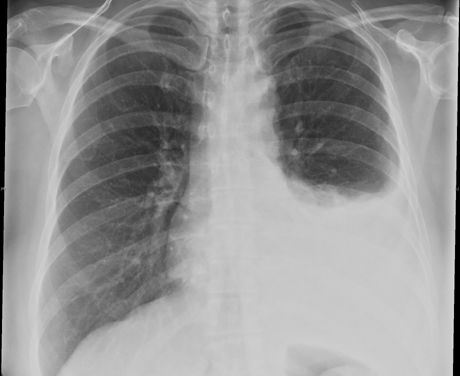

Загадки медицины: Эмпиема легких на рентгене